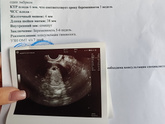

Вот я наконец-то сходила на узи ииии...

Нашли моего малыша! ????

Как я рада, не могу поверить, моя бусинка показалась??☺

Сердечко еще рано, но врач сказал движения есть, через недельку повторить узи. Слава богу ???